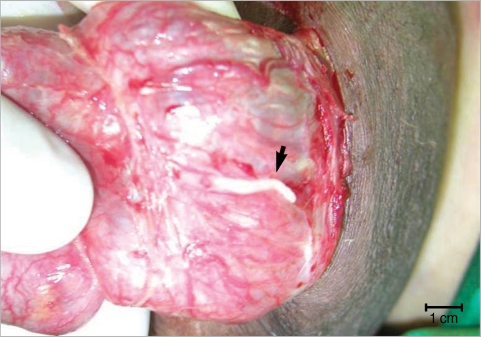

At operation, multiple spargana were found within the mass, around the spermatic cord and scrotal soft tissues (Figs. 1, 2). All identified spargana worms were completely excised. Diagnostic cystoscopy was performed consecutively to evaluate the microscopic hematuria, and a 10-mm sized small nodular mucosal elevation was found in the right side of the dome of the urinary bladder (Fig. 3). Covered mucosa was removed using resectoscope, and a whitish worm-like mass surrounded by granulation tissues was found inside of the nodule (Fig. 4). We tried to remove it by forceps, but it came apart. Histological examinations revealed a foreign body granuloma with a few infiltrates of eosinophils. In a serological test, patient's serum showed a positive reaction to anti-sparganum IgG antibody.

Humans can be infected by spargana via ingestion of contaminated water, eating raw amphibian (frog) or reptile (snake) meat, or dermal contact of those meats as a poultice. The ingested spargana can invade various organs, such as the eye, subcutaneous tissues, abdominal wall, brain, spinal cord, lung, breast, and others [3-5]. In the case of genitourinary system, the scrotum was the most commonly affected organ by the spargana [6]. Also an involvement of the epididymis, spermatic cord, penis, retroperitoneum, and ureter has been reported [2,7,8]. So far, only 1 case of vesical sparganosis has been reported which caused eosinophilic cystitis [9]. However, the diagnosis was based on elevated serum IgG antibodies for spargana and the histopathological findings with infiltrated eosinophils, but not by the worm. In our study, we directly removed the worm by forceps under cystoscopy from the submucosa of the bladder, and confirmed sparganosis by a PCR reaction. Therefore, this is the first case of urinary bladder sparganosis confirmed by the worm (PCR) among the literature.